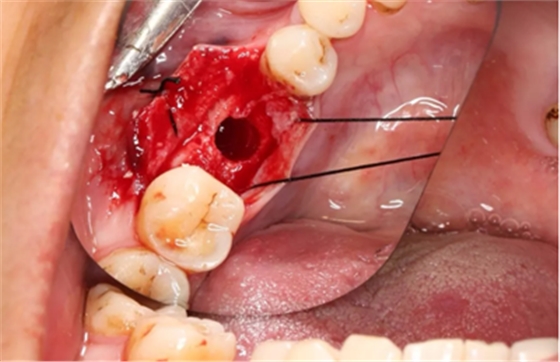

6、牙槽嵴保存术过程:拔牙及位点保存

(摄于2016年8月31日)

11、常规植入WEGO种植体一颗

牙槽嵴顶水平切口,翻瓣,牙槽嵴近中较远中丰满。

(摄于2017年4月14日)

12、延期种植手术过程

使用直径3mm的环形取骨钻切取长约9mm的柱状骨标本,用于组织学和显微影像检查

由于取骨致窝洞较大,加之缺牙间隙大,只好选择植入5mm直径种植体;种植备洞完成后,颊侧骨壁厚度仅约1mm。